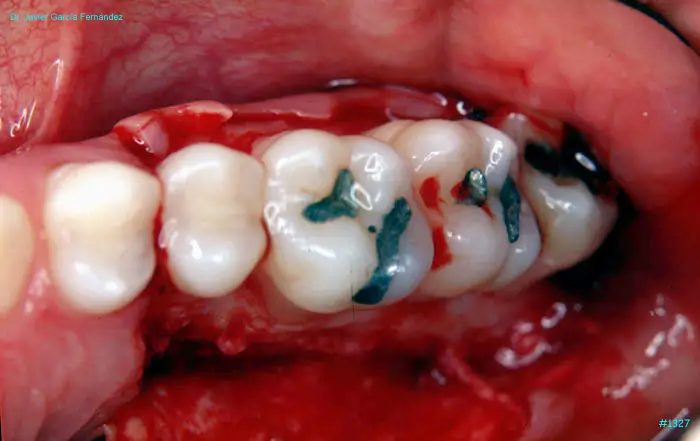

Atlas of Surgical Techniques in Periodontics. Chapter III. Atlas de Técnicas Quirúrgicas en Periodoncia